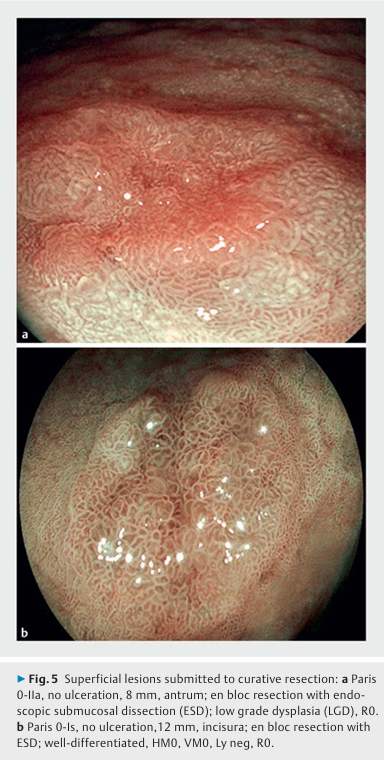

▶Fig.5와 ▶Fig.6은 표재성 병변의 내시경 이미지를,

▶Fig.7은 신생물 병변은 없으나 전암성 병변의 다양한 단계를 보여주는 위 내시경 이미지를 제시한다.